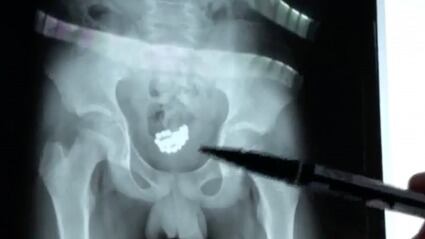

A un niño de 13 años en el norte de China se le extrajeron 29 bolitas magnéticas de la vejiga después de insertarlas en su pene.

En otro clip, un médico también mostró las 29 cuentas magnéticas a la cámara después de haber sido retiradas del niño a través de la cirugía.

Según los informes, el niño curioso insertó las cuentas magnéticas en su pene y no las sacó.

Finalmente, los médicos retiraron las 29 bolas magnéticas de su cuerpo y él continúa recuperándose en casa. Video: Reuters.